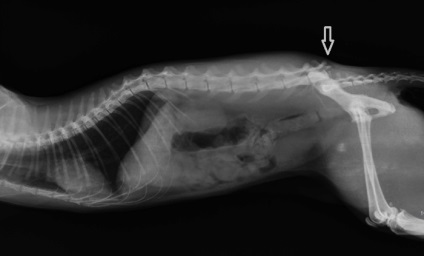

Hogyan állapítható meg, a csigolyatörés egy kutya? Általában diagnózist lehet már alapján szemrevételezéssel és tapintással. Súlyos esetekben, amikor feltörtek, és a mélysége a seb csatorna töredékei csontok látható ok kételkedni nem szükséges. Mégis minden kétség esetén, azt mutatja, egy X-ray. A nehézség abban rejlik, hogy megfelelően állat-egészségügyi szakértői a világ minden tájáról, egyértelműen látható repedés nem több, mint 75% -ában. Egy kis elmozdulás azonos vagy repedés sokkal nehezebb diagnosztizálni. Így azokban a helyzetekben, nehéz és vitatható ajánlott kontrasztos röntgenvizsgálata, amelynél csigolya sérülés lesz jól látható (inkább).